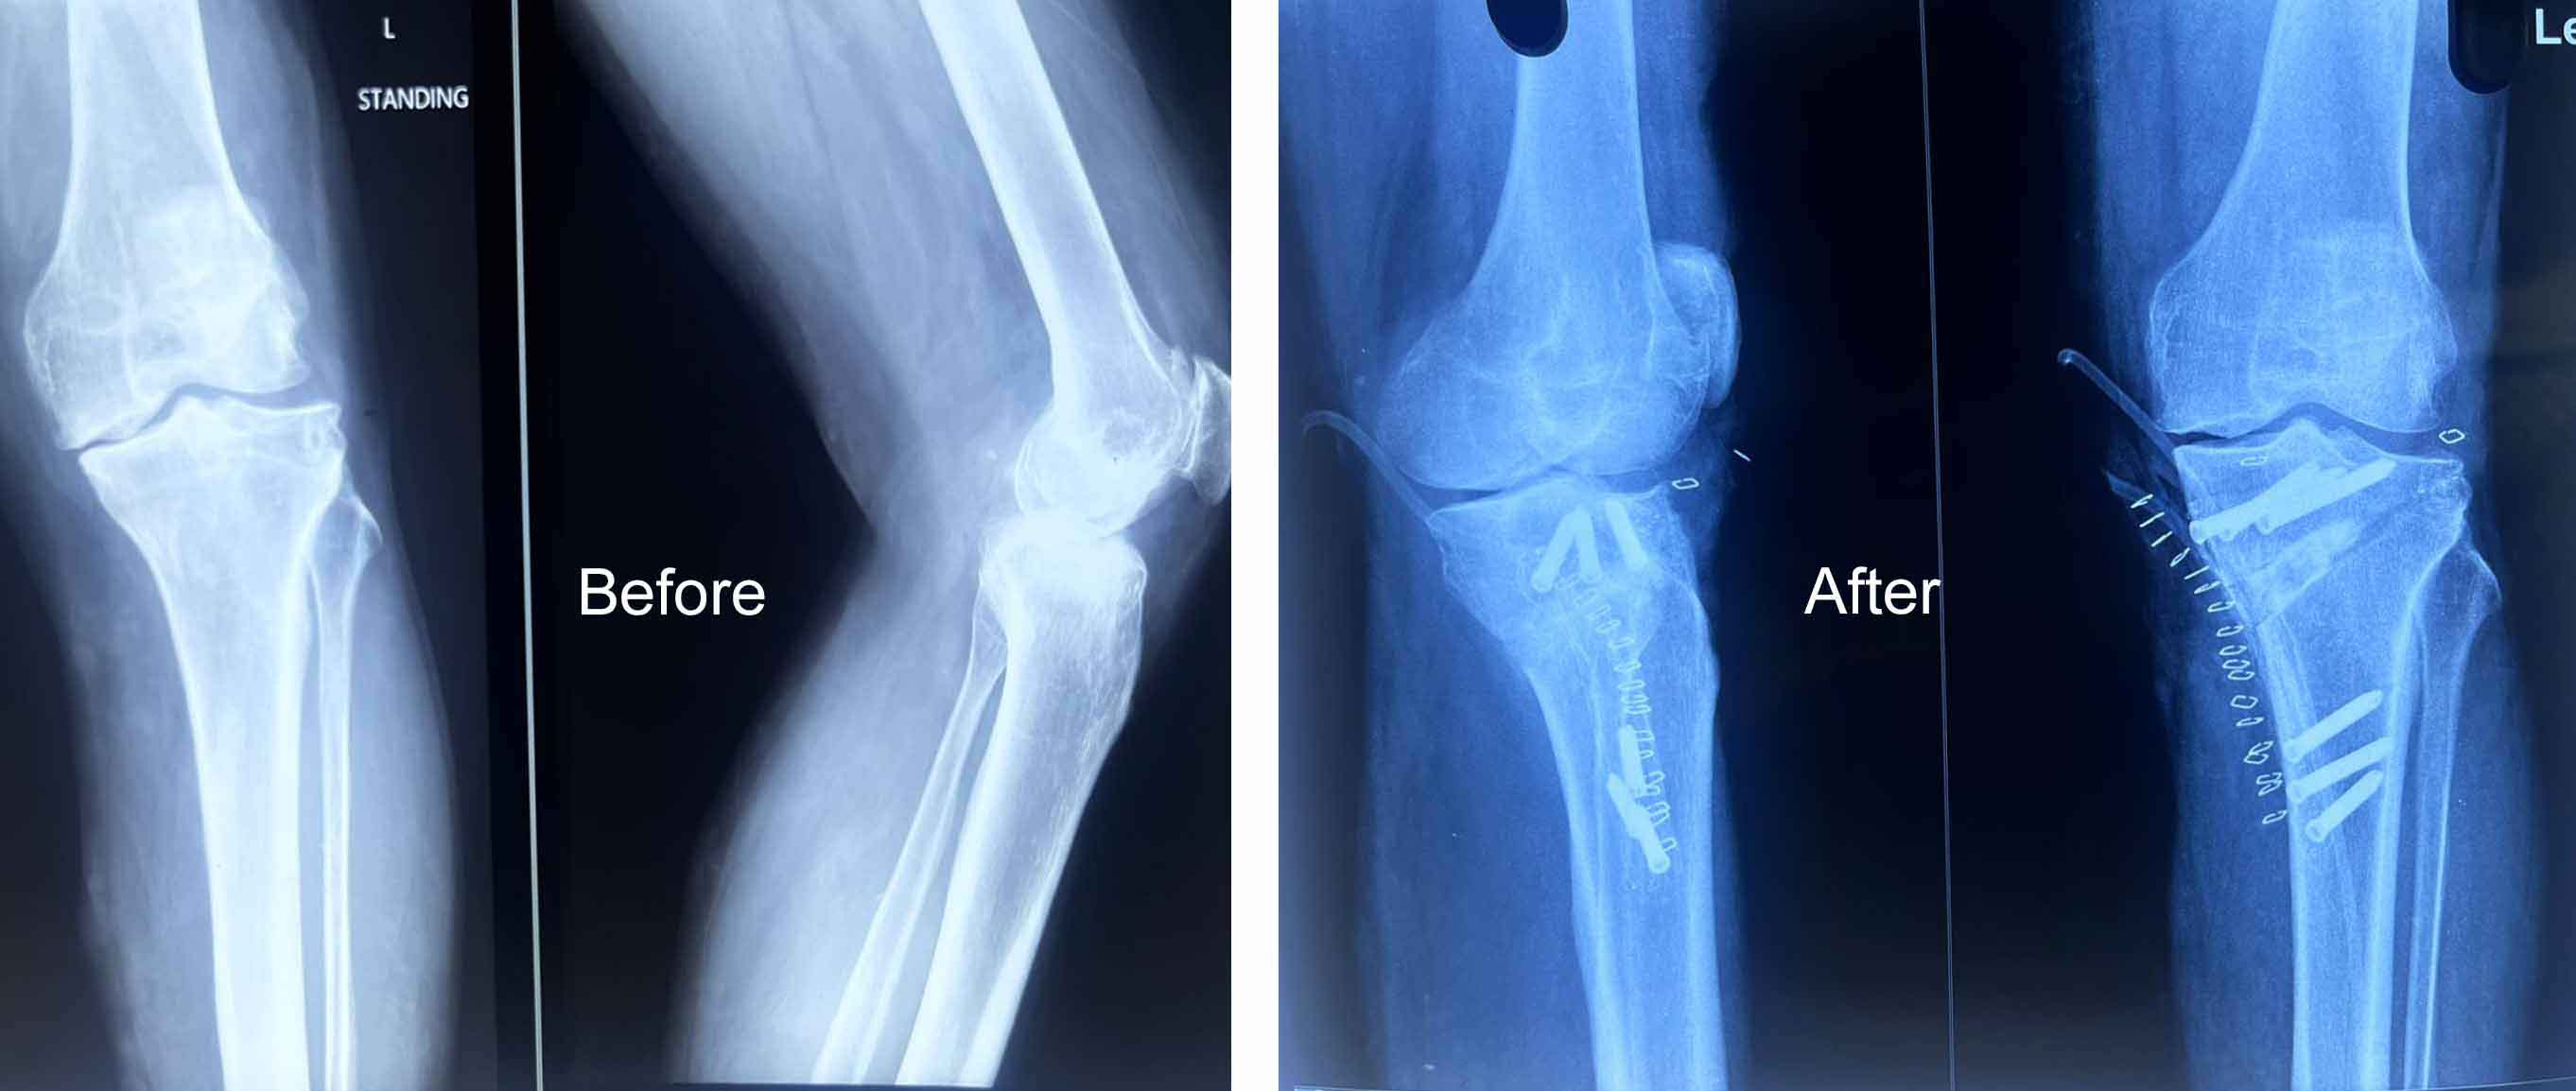

Medical Gallery

Orthopedic Care